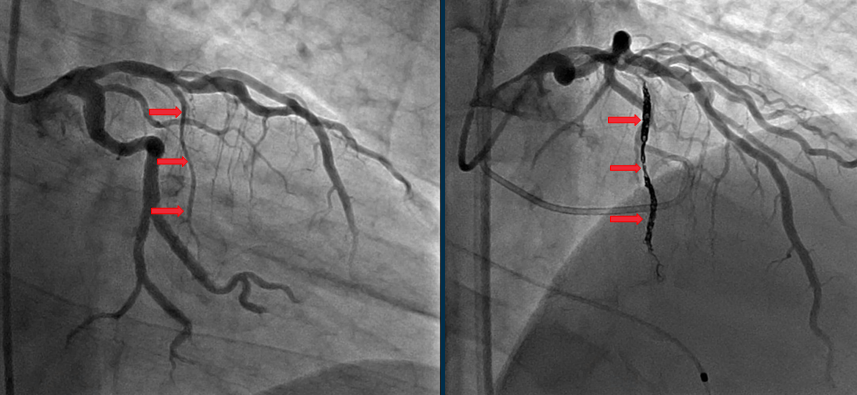

造影评估:通过冠状动脉造影明确冠状动脉解剖结构,识别供应肥厚室间隔的目标穿支动脉;

导管定位:将微导管送至目标间隔支动脉,通过微导管注射造影剂,确认该血管为供应梗阻区域的责任血管;

弹簧圈植入:将可解脱弹簧圈通过微导管送至目标血管内,根据血管直径和血流情况,进行致密弹簧圈填塞,直至血管血流完全阻断;

术后验证:再次通过造影确认目标血管栓塞效果,通过导管测量LVOT压差,评估即刻疗效。